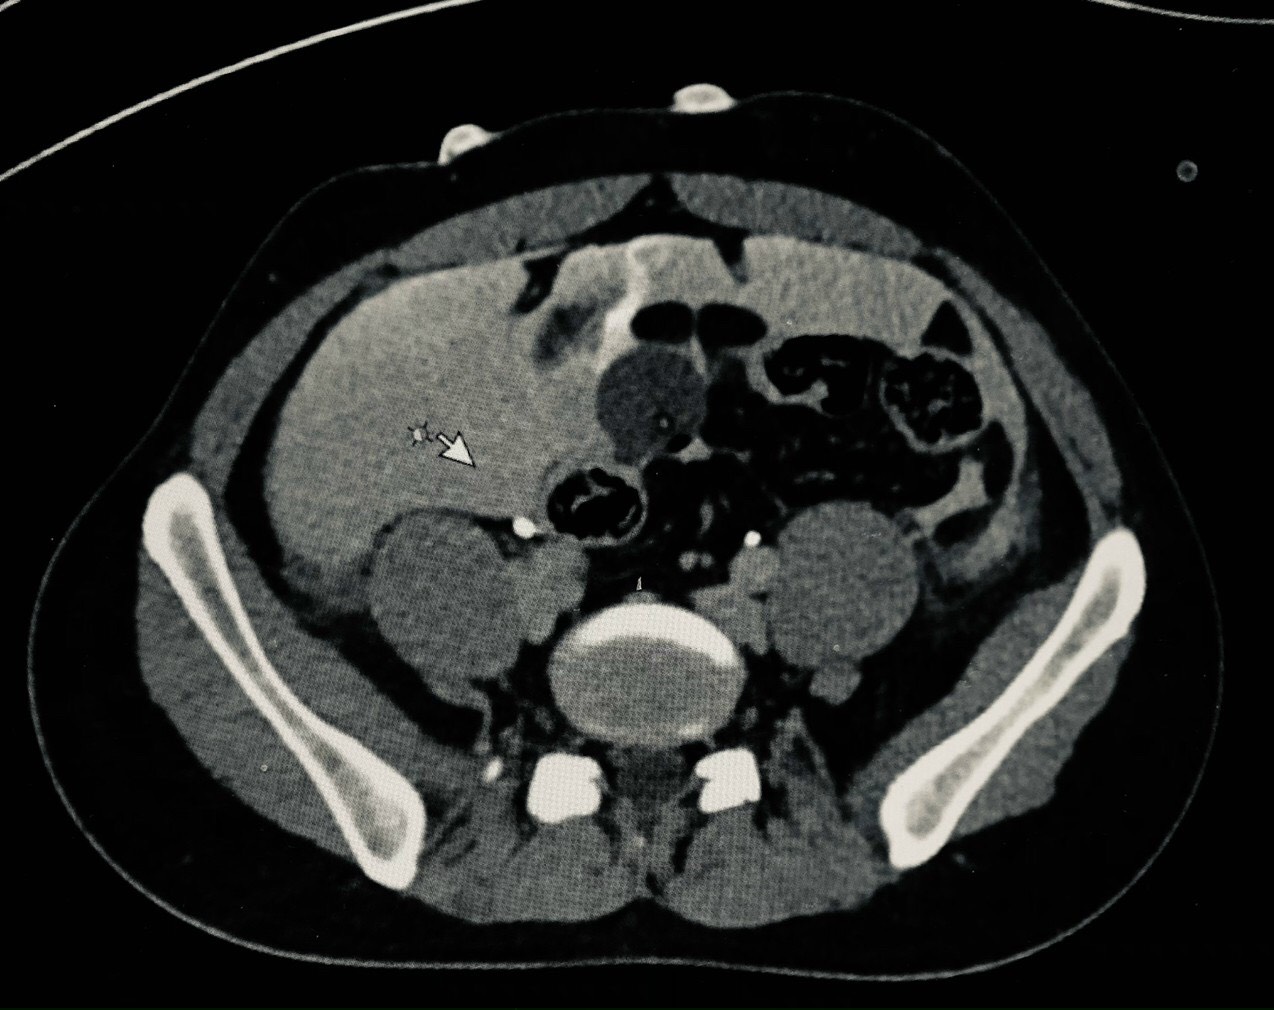

Hình ảnh chụp CT của bệnh nhân T